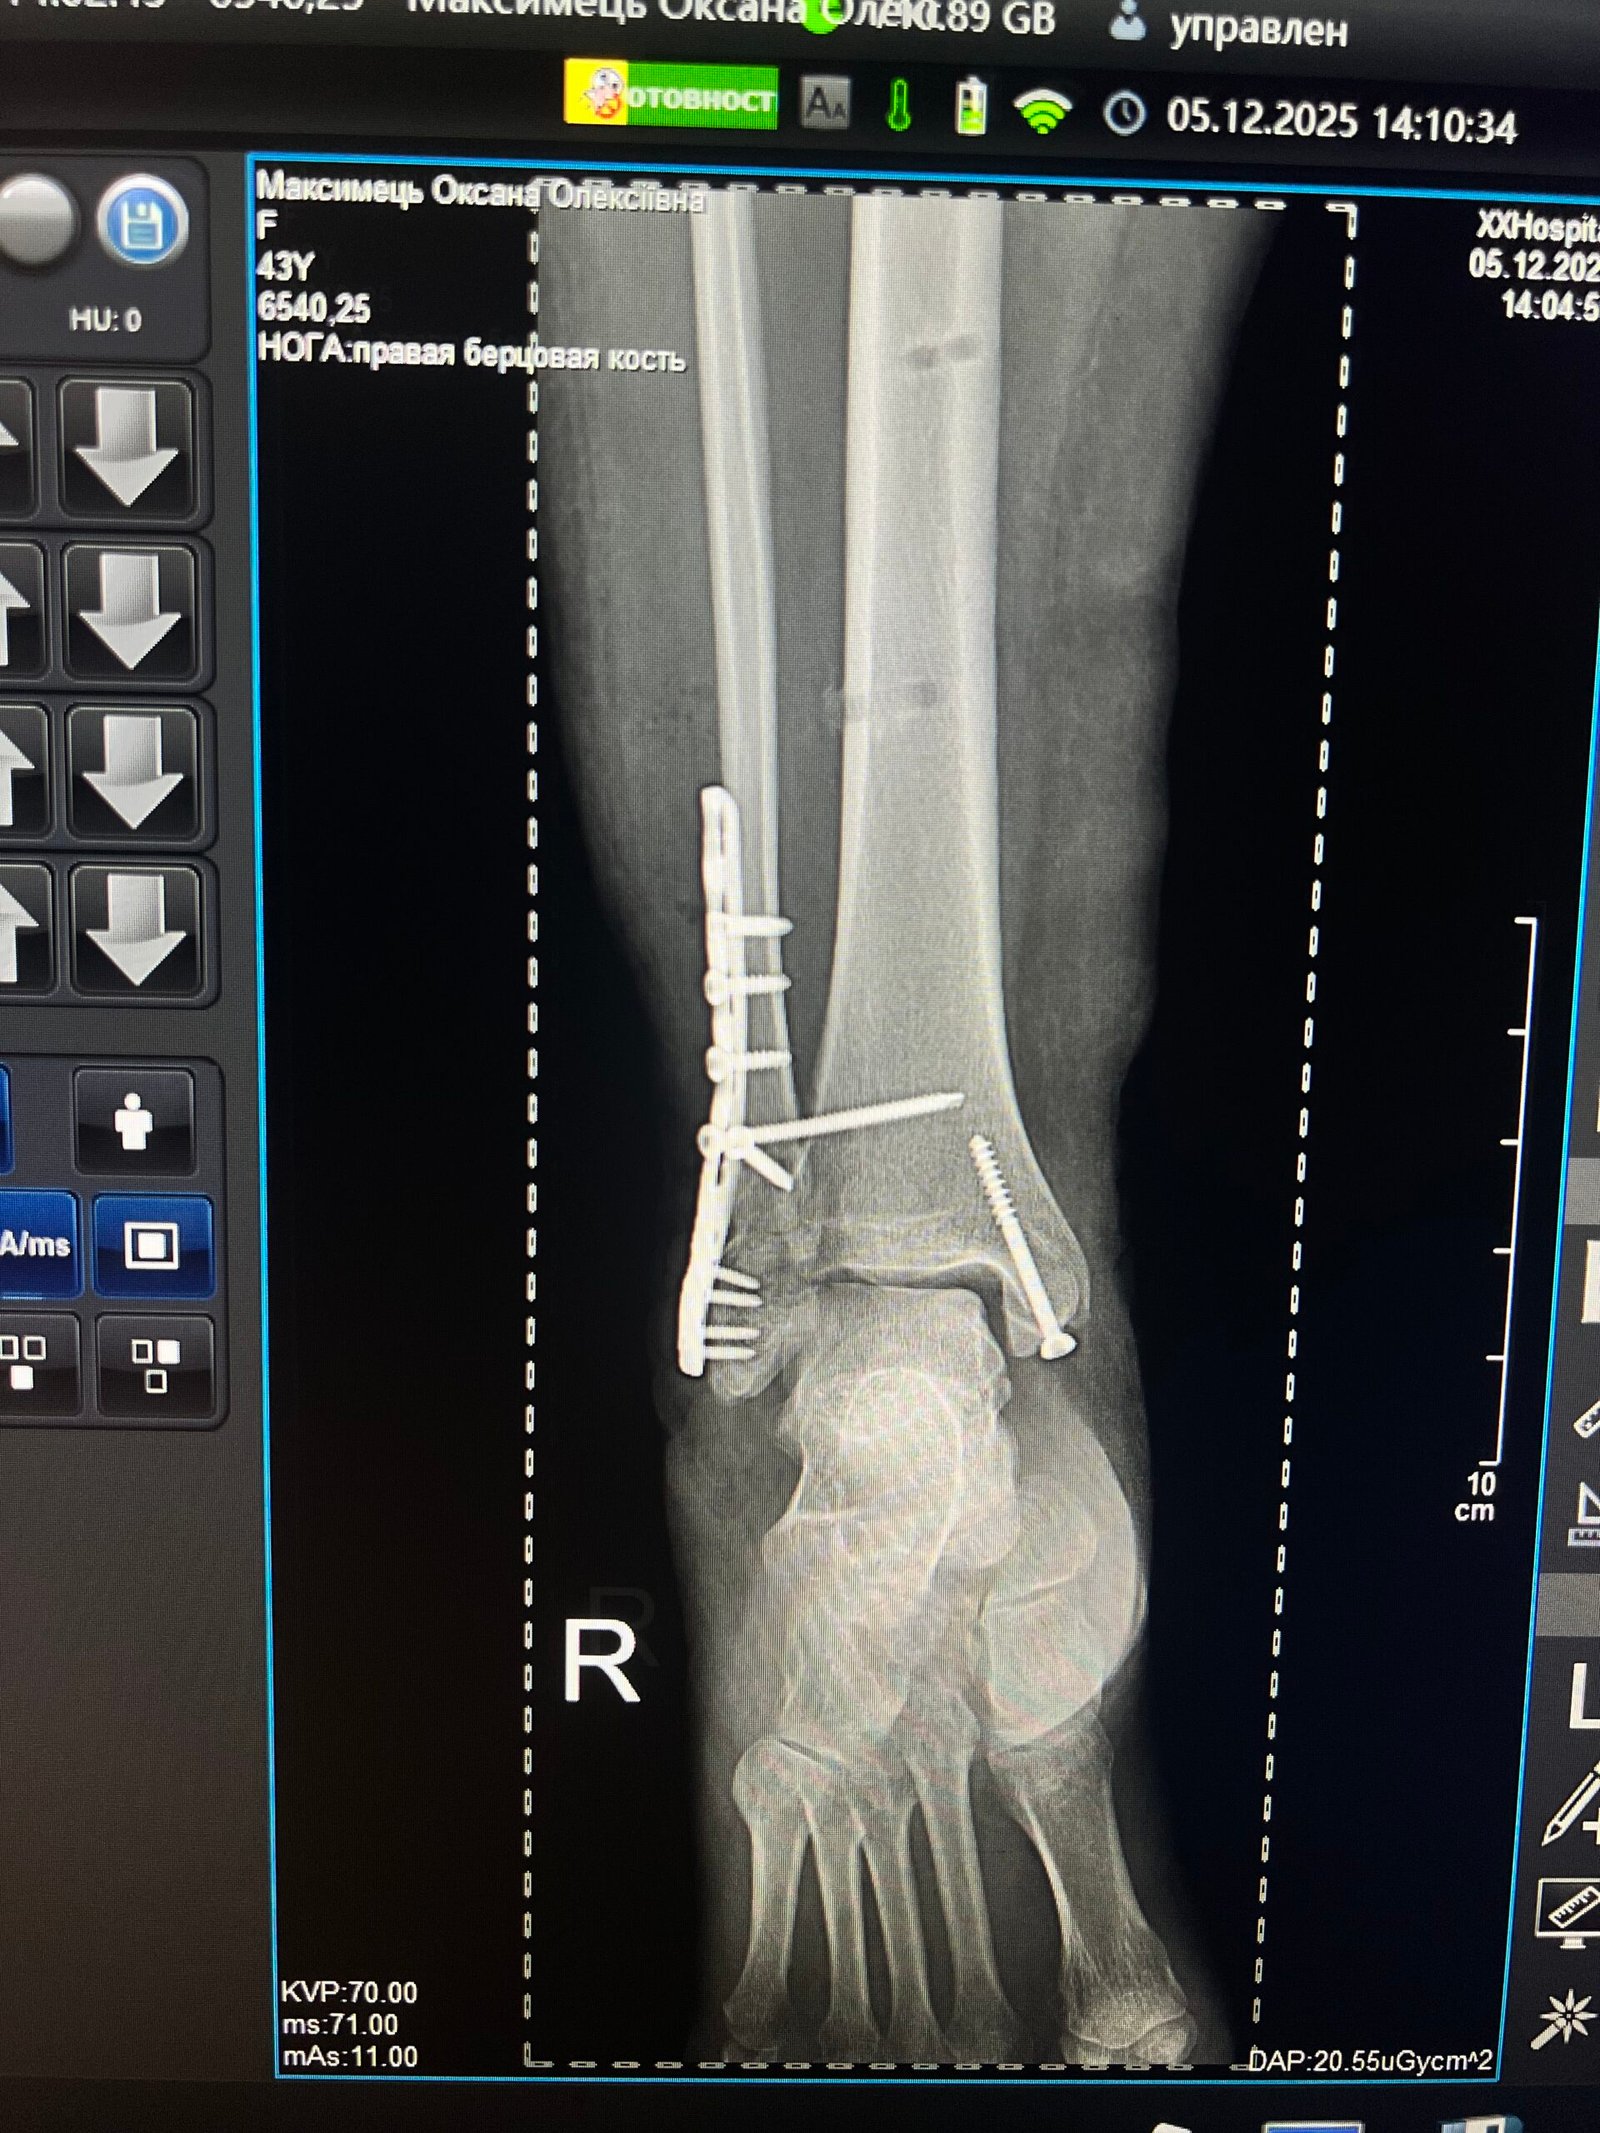

З дня аварії минуло більше року, було проведено не одну операцію на ногу, коли вже думала, що все позаду, і тут повторний рентгент та невтішний результат: перелом не зрісся, остомеліт, пластина не прижилась. Лікарі відправили в Київ на консультацію, там сказали , що якщо не знайду у Львові лікаря , який погодиться мене прооперувати , тоді приїхати до них. Дякувати Богу, зустріла знайомого, який порекомендував мені лікаря ортопеда-травматолога – Досяка Мирослава Ігоровича. Коли я прийшла до нього на консультацію, думала , що знову почую відмову, як і від інших лікарів. Він довго роздивлявся рентгенівські знімки , оглядав ногу, розпитував, що сталося, і тут сказав: “Я тоговий вас прооперувати, я візьмусь за лікування вашої ноги, не хвилюйтеся, все буде добре”.

Вже через 5 днів операцію було успішно проведено.

Лікування було проведено в декілька етапів. Оскільки у пацієнтки при огляді діагностовано септичну нестабільність металофіксаторів, хронічний остеомієліт великого мілкової кістки та стійку еквіно-варусну деформацію стопи(“кінська стопа”) першим етапом виконано видалення пластини, санація рани та позавогнищевий остеосинтез апаратом Ілізарова. Другим етапом виконано перемонтаж АЗФ та поступова керекція еквіно варусної деформації стопи в апараті Ілізарова.

Виконували бойове завдання неподалік селища Спірне Бахмутського району Донецької області. Під час мінометного обстрілу отримав поранення гомілковостопного суглоба, який був повністю зруйнований осколками. Відвідав не один медичний заклад, думки лікарів щодо вирішення моєї проблеми були різними. З Досяком Мирославом Ігоровичем познайомився випадково через знайомих, його підхід до операції мені дуже сподобався і підходив, оскільки в Мирослава Ігоровича є великий досвід у подібних ситуаціях, особливо з військовими. Операцію проводив Мирослав Ігорович разом із Тарасом Олеговичем у Першій міській лікарні м. Львова, і вона пішла на користь, оскільки після неї я міг сміливіше ставати на ногу без тих болів, що були до операції. Хочу щиро подякувати Мирославу Ігоровичу, Тарасу Олеговичу та всьому персоналу Першої міської лікарні за їхню роботу та ставлення до мене й до інших пацієнтів лікарні, з якими я перебував там під час тривалого лікування. Щира подяка Вам!